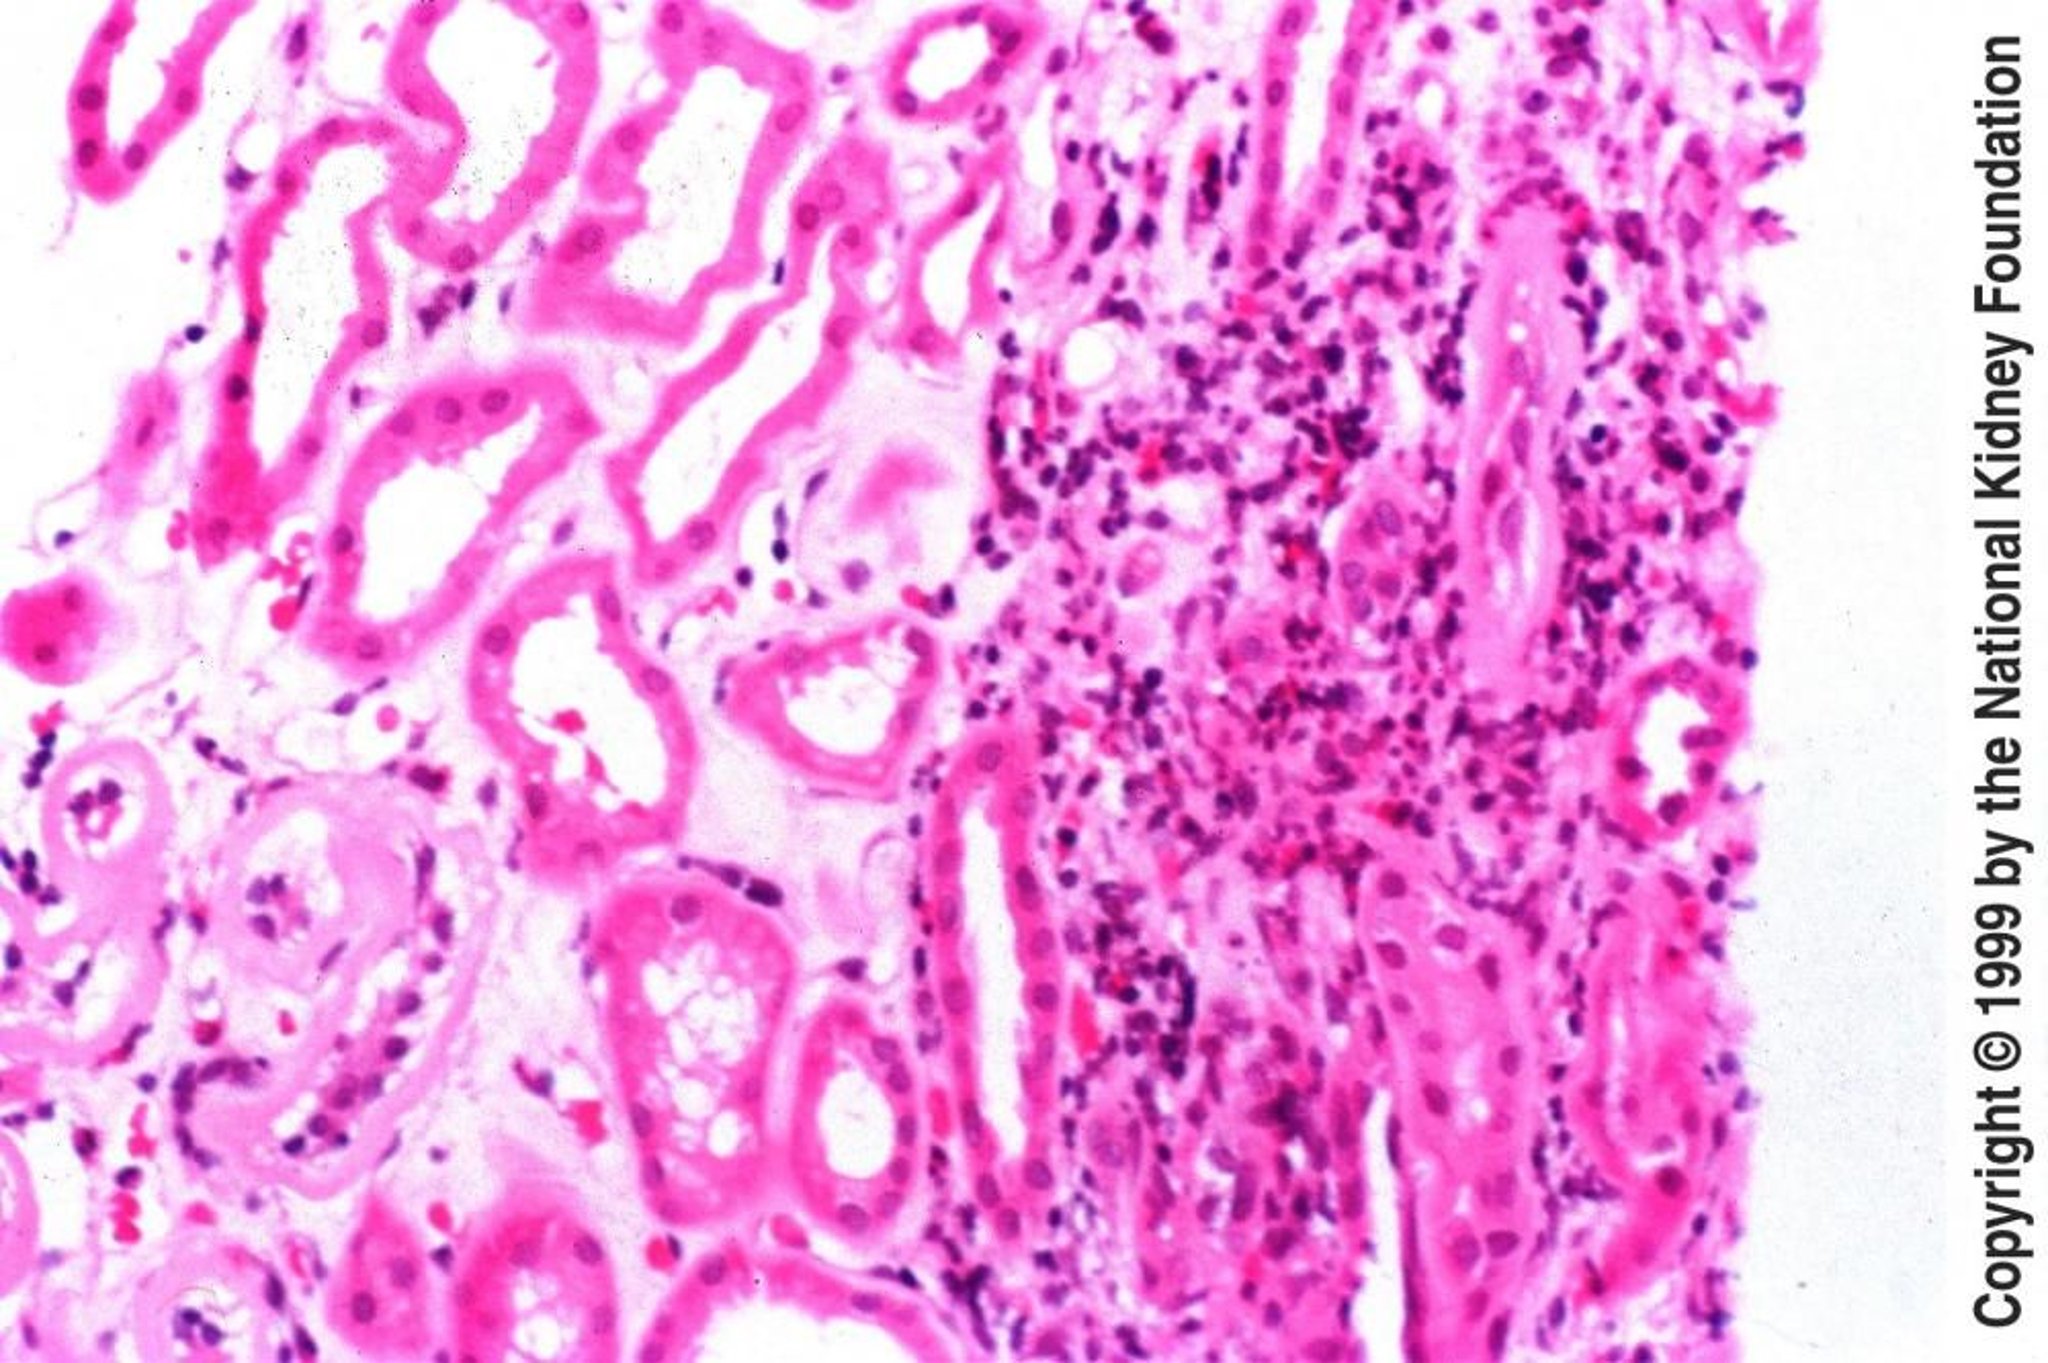

Nefritis tubulointersticial aguda

La pieza de biopsia de la nefritis tubulointersticial aguda muestra edema intersticial con infiltración de eosinófilos, linfocitos y células plasmáticas (tinción de hematoxilina-eosina, ×200).

Image provided by Agnes Fogo, MD, and the American Journal of Kidney Diseases' Atlas of Renal Pathology (véase www.ajkd.org).